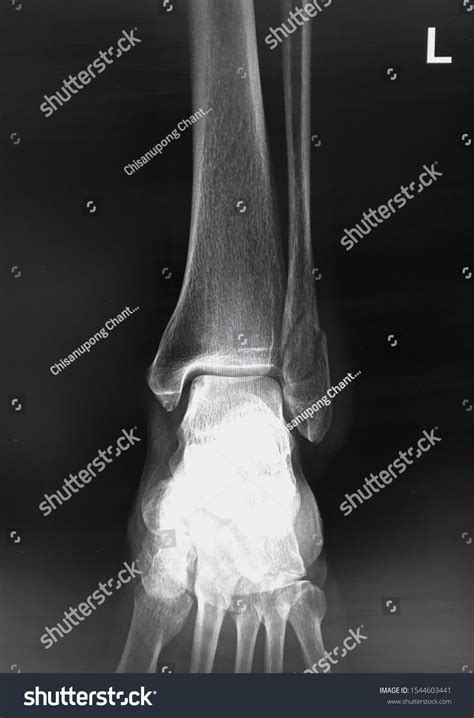

A Lateral Ankle Xray is a specific type of X-ray that provides a side view of the ankle. This view is particularly useful for assessing the alignment of the bones and identifying fractures or dislocations. The lateral view complements other views, such as the anteroposterior (AP) and mortise views, to give a comprehensive picture of the ankle's condition.

Interpreting a Lateral Ankle Xray requires a trained eye to identify key features and abnormalities. Some of the important aspects to look for include:

• Bone alignment: Ensuring that the bones are properly aligned and there are no signs of fractures or dislocations.

• Joint space: Assessing the width and uniformity of the joint space to detect any signs of arthritis or other joint issues.

• Soft tissue swelling: Identifying any swelling or inflammation around the ankle that may indicate an injury.

Radiologists and orthopedic specialists are trained to interpret these images and provide a detailed report of their findings. This report is then used to guide treatment decisions.

Common Findings on Lateral Ankle Xray

Some of the common findings on a Lateral Ankle Xray include:

• Fractures: Visible breaks in the bones, which may be simple or complex.

• Dislocations: Misalignment of the bones, often due to severe trauma.

• Osteoarthritis: Changes in the bone structure and joint space indicative of degenerative joint disease.

• Soft tissue swelling: Inflammation or edema around the ankle, which may be due to injury or infection.